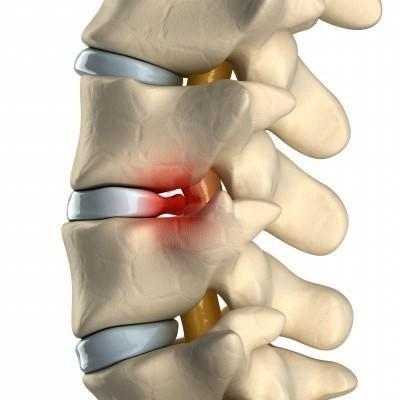

Компрессия нерва при остеохондрозе шейного отдела позвоночника ( грыжей или протрузией межпозвонкового диска, спондилезе, спондилоартрозе и стенозе позвоночного канала) — это ещё одна распространённая причина боли в шее и руке. Компрессия может возникнуть на уровне позвоночника, в том месте, где нервы выходят из спинного мозга и направляются к руке.

Компрессия нервного корешка на уровне шейного отдела позвоночника также называется сдавлением или защемлением нерва. При стенозе (сужении) позвоночного канала отверстия, через которые проходят нервы, сужаются, что приводит к защемлению спинномозгового нерва частью кости. Сдавление шейного нервного корешка (шейная радикулопатия) возникает на уровне шейного отдела позвоночника и может вызывать множество различных симптомов. Для грыжи или протрузии шейного отдела позвоночника характерны такие симптомы, как головокружение, скачки артериального давления, головные боли, боль в плече, руке, шее, онемение пальцев руки.

Межпозвоночная грыжа

Вытекая через трещины фиброзного кольца в позвоночный канал, пульпозное ядро оказывает давление на нервные корешки, вызывая тем самым мучительные боли.

Боль локализуется в шее, плече и руке. Характеризуется как острая, становится интенсивнее при повороте головы, чихании, кашле. Болит шея и плечо меньше при заведении руки за голову.